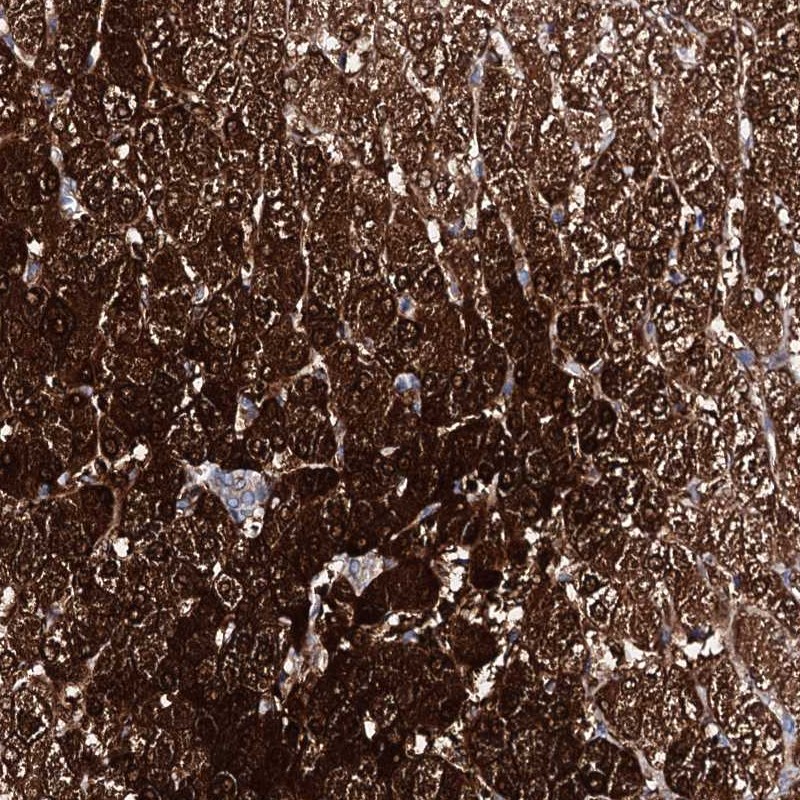

Immunohistochemical staining of human liver shows strong cytoplasmic positivity in hepatocytes.